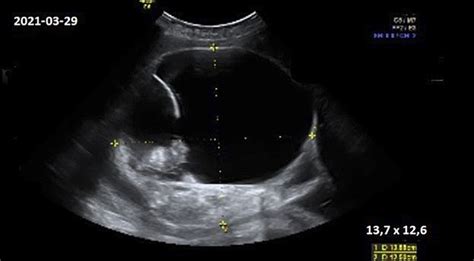

Placentos pirmeiga dažniausiai nustatoma planinio antrojo trimestro ultragarsinio tyrimo metu (apie 18-22 nėštumo savaitę). Tiksliausiai placentos padėtį leidžia įvertinti transvaginalinis ultragarsinis tyrimas (kai daviklis įvedamas į makštį) - jis yra saugus tiek mamai, tiek vaisiui. Ultragarsinis tyrimas yra pagrindinis ir patikimiausias būdas diagnozuoti placentos pirmeigą.

Patologinis placentos prisitvirtinimas diagnozuojamas ultragarsinio tyrimo metu. Pirmojo nėštumo trečdalio ultragarsinės patikros metu gydytojas akušeris-ginekologas, prižiūrintis nėštumą, turi pažymėti placentos prisitvirtinimo vietą ir įvertinti, ar nėščioji turi patologinės placentos prisitvirtinimo rizikos veiksnių. Antrojo nėštumo trečdalio metu patologinės placentos prisitvirtinimo požymiai būna jau ryškesni, o galiausiai diagnozė nustatoma 28-32 nėštumo savaitę.